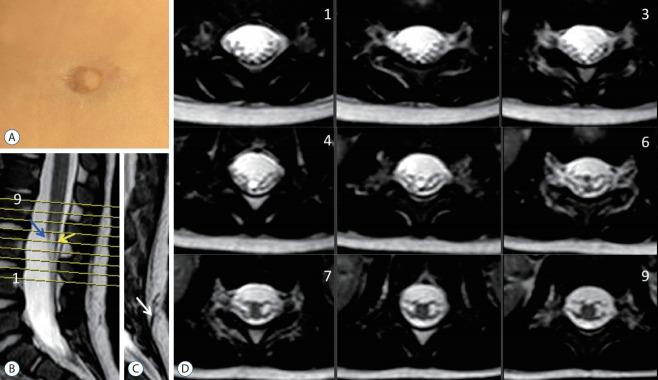

Spinal dysraphic lesions due to focal nondisjunction in primary neurulation are commonly encountered in paediatric neurosurgery, but the "fog-of-war" on these conditions was only gradually dispersed in the past 10 years by the works of the groups led by the senior author and Prof. Kyu-Chang Wang. It is now clear that limited dorsal myeloschisis and congenital spinal dermal sinus tract are conditions at the two ends of a spectrum; and mixed lesions of them with various configurations exist. This review article summarizes the current understanding of these conditions' embryogenetic mechanisms, pathological anatomy and clinical manifestations, and their management strategy and surgical techniques.

由于原发性神经管形成过程中的局灶性不分离导致的脊柱裂病变在小儿神经外科中很常见,但在过去10年中,由资深作者和王宇辰教授领导的团队的工作才逐渐驱散了这些病症上的“战争迷雾”。现在已经明确,有限性背侧脊髓裂和先天性脊柱皮样窦道是同一谱系两端的病症;并且存在各种形态的它们的混合病变。这篇综述文章总结了目前对这些病症的胚胎发生机制、病理解剖和临床表现,以及它们的治疗策略和手术技术的认识。